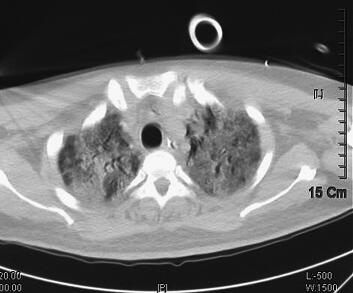

辅助检查:2011年4月5日胸部CT示双肺感染(图1)。血气分析:pH 7.40,PCO2 38.2mmHg,PO2 35.6mmHg,22.9mmol/L,BE −0.7mmol/L,SBE −1.0mmol/L,SaO2 65.0%,提示低氧血症;血常规:WBC 16.8×109/L,Hb 172g/L,PLT 56×109/L,N 0.917;急诊生化:ALT 89IU/L,TBTL 49.0μmol/L,Glu 7.64mmol/L,UREA 14.30mmol/L,CREA 132μmol/L,cTnI 0.04ng/ml。

图1 2011年4月5日胸部CT示双肺感染